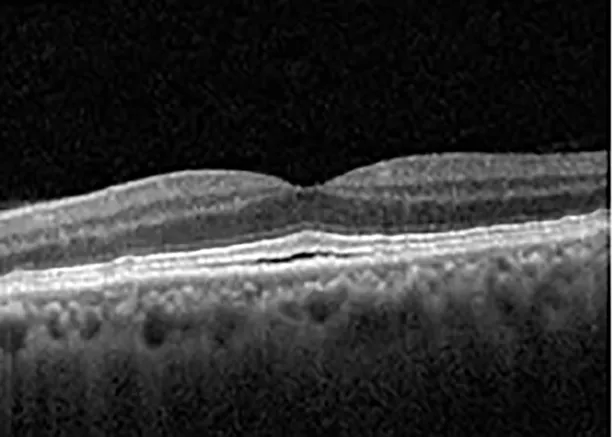

The patient began treatment with oral pemigatinib daily and was followed up for an ophthalmic examination during the second treatment cycle approximately 5 weeks into the treatment process. The patient had at this stage received 28 doses of 13.5 mg per day, which was administered in cycles of 14 on-days and 7 off-days, and had no visual or ophthalmic complaints. The non-corrected VA was OD 20/30 + 1 and OS 20/20. The OCT examinations revealed subfoveal SRF bilaterally. The fundus examination was otherwise unremarkable outside the patient’s prior documented peripheral drusen. Repeat autofluorescence was overall unchanged, though a slight hypofluorescent ring may be visualized in Figure 2. The current pemigatinib protocol recommendation for asymptomatic patients suggests no dose modification; however, with worsening presentation or positive symptoms, it is recommended to withhold pemigatinib. After discussion with the patient’s oncologist, it was decided to continue the medication at this time. Serial monitoring of the patient’s symptoms, vision, and SRF were conducted on specific days during active treatment cycles and days off-cycle to monitor the SRF. Subsequent evaluations demonstrated complete resolution of SRF while off-cycle, and asymptomatic re-accumulation of fluid while on-cycle with varying levels of VA. (Table 1) As we see demonstrated in the table below, in the later stages of the active cycles, such as day 13 of 14 of cycle 2, day 13 of 14 of cycle 3, day 13 of 14 of cycle 4, and day 14 of 14 on cycle 5, the patient’s VA showed no correlative changes based on the presence of SRF. The fluctuations in the patient’s VA certainly occurred, but were likely to be secondary to surface changes, as certain off-cycle days actually presented with lower acuities than days when the SRF was present on OCT examination.

| Cycle, day, on/off | VA OD; OS | CMT OD; OS | OCT OD | OCT OS |

| Cycle 5, day 14/14, on | 20/30−1; 20/20 | 375; 364 | ![]() | ![]() |

Highlights the visual acuity, central macular thickness, and the physical OCT of the macula for this patient in both the right and left eyes during various stages of the patient's chemotherapy treatment cycle.